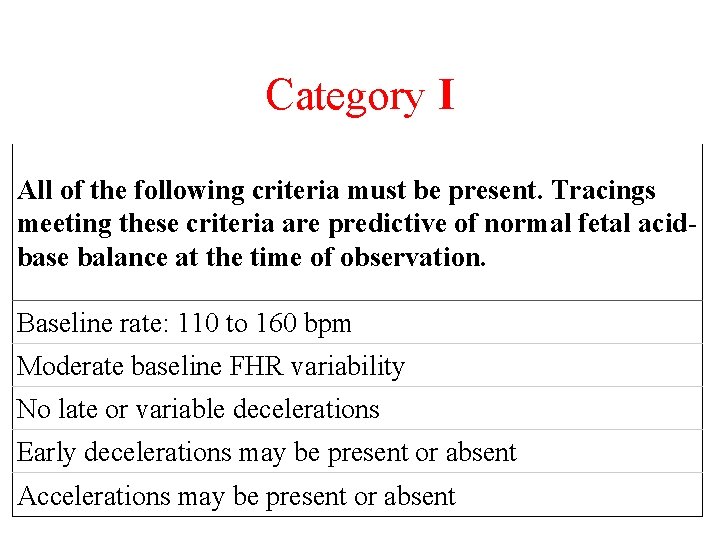

Category I All of the following criteria must be present. Tracings meeting these criteria are predictive of normal fetal acidbase balance at the time of observation. Baseline rate: 110 to 160 bpm Moderate baseline FHR variability No late or variable decelerations Early decelerations may be present or absent Accelerations may be present or absent